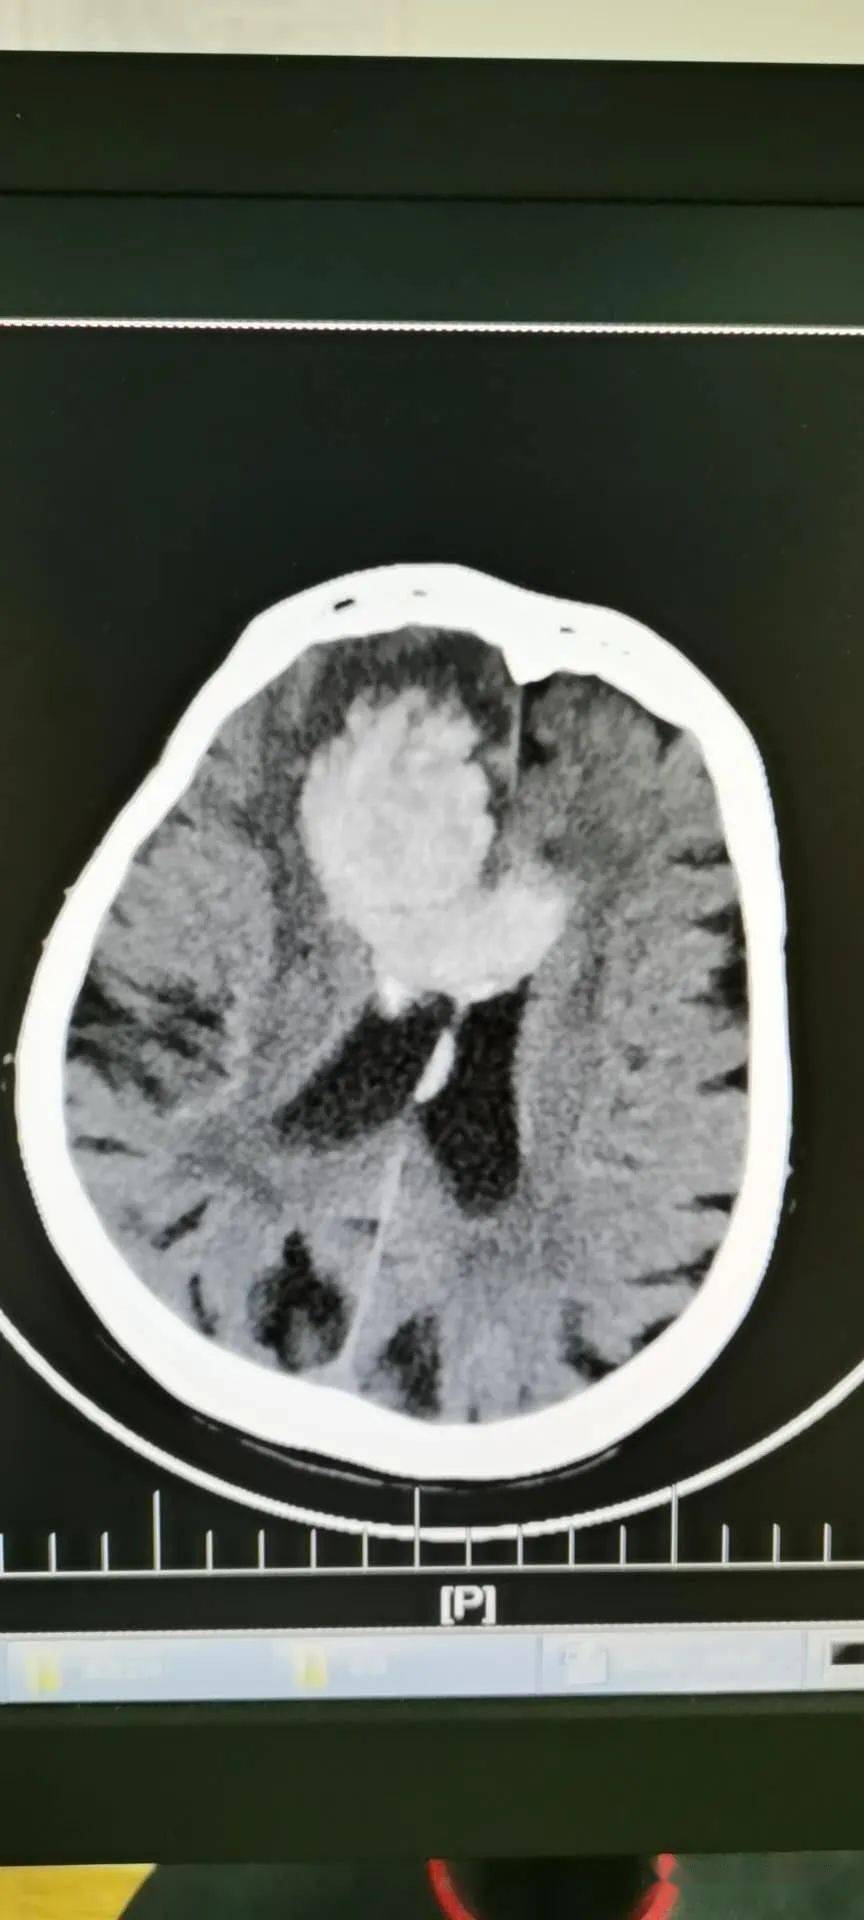

头部ct平扫见左顶叶大片状低密度,呈指套样伸向皮层,提示白质脑水肿